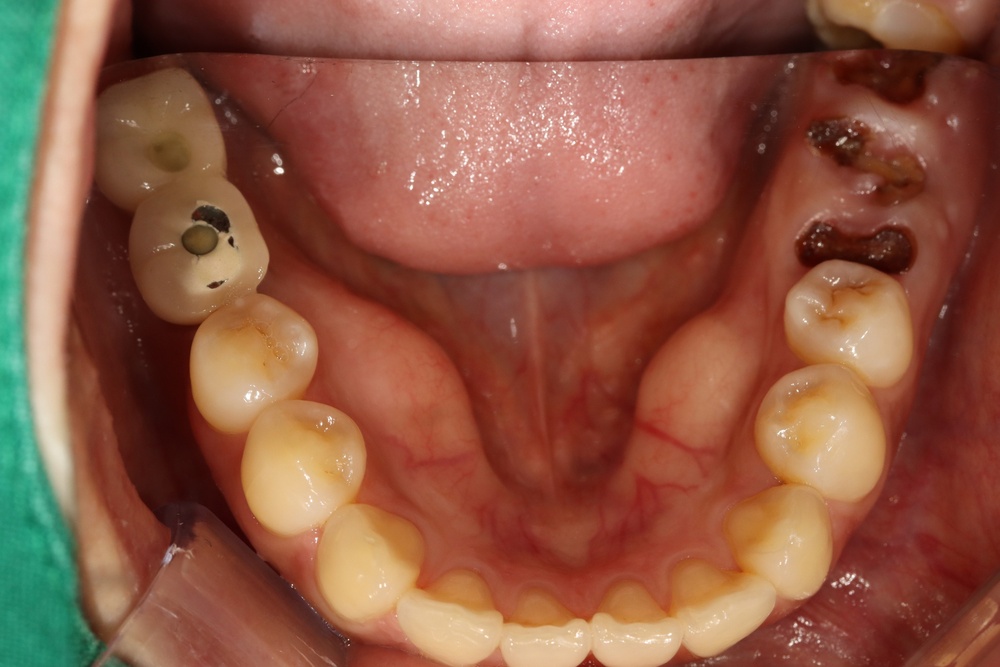

충치가 많아서 교정 전 충치치료를 전반적으로 시행하고, 잇몸치료도 진행하였습니다.

아래쪽 두 번째 어금니(제2대구치)가 선천적으로 없는 결손치로서, 사랑니(제3대구치)가 있으나 앞으로 쓰러져서 잘 안 씹히고 썩어 있습니다.

부분교정을 통해 누워있던 사랑니를 세웠으나, 씹는 면에 충치가 있습니다.